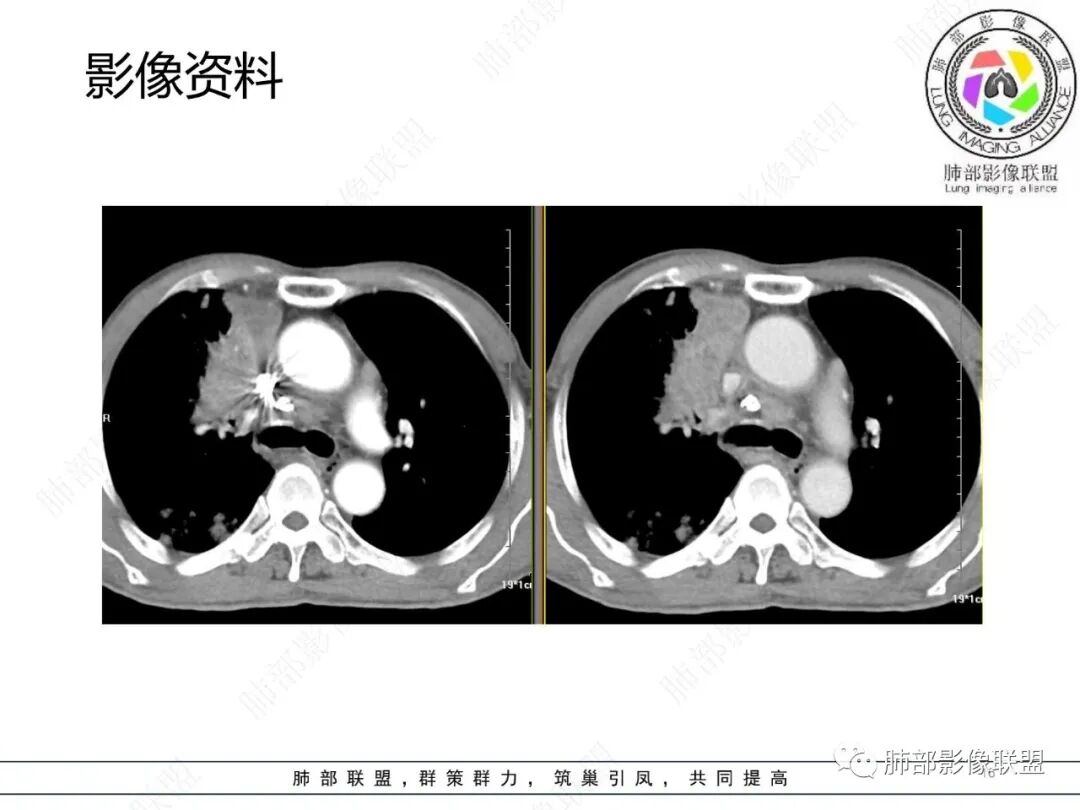

影像资料

2.胸部CT: 右肺病灶,主要累及右肺上叶前段、右肺中叶内侧段及右肺下叶背段,片状影及结节影,实性密度为主,部分磨玻璃晕,密度不均,散在钙化,其中上叶前段支气管闭塞,隐约见钙化突入。未见明确“硬树芽”或“拐枣征”。主要呈延迟强化,其间低密度区疑坏死或粘液成分。纵隔内见多组淋巴结肿大环形强化,部分钙化。